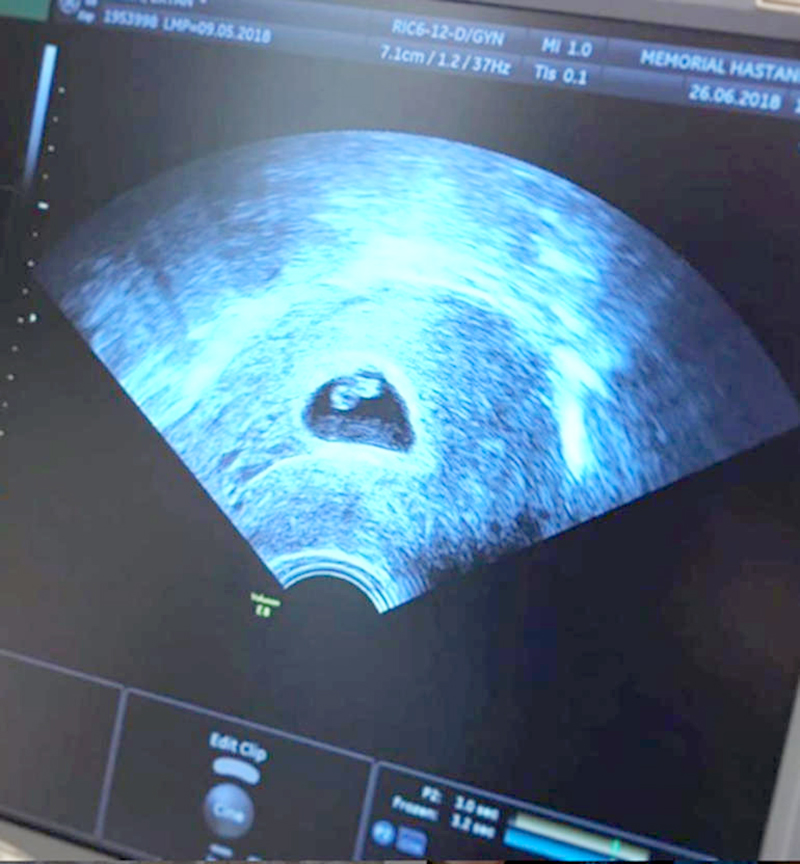

İşadamı Ersin Kayalar ile 28 Nisan’da evlenen Siren Ertan iki aylık hamile. Dün kontrol için eşi ile birlikte doktora giden Siren Ertan, can sıkıcı bir durumla karşılaştı.

“Biz bugün doktorumuza gittik. Kalbinin sana kavuşmaya can atan benim kalbim kadar hızlı atamadığına çok üzgünüm bebeğim. Ben seni sımsıkı tutuyorum, sen de hayata tutun ne olur. Ben seni nasıl bir özlemle bekliyorum bir bilsen. Sen yoksun diye ben yıllarca ne ağladım bir bilsen.

Bil ki sen bana gelirsen ömrüm boyunca kıymetini bileceğim senin. Bil ki çocuklarına “öf” diyen ebeveynlerden olmayacağım. Çünkü onlar bilemezler ki yokluğunun ne demek olduğunu. Yeter ki sen güçlü ol, bizimle kal. Bu sana ilk mektubum. Annen yazmayı sever ama belki bir daha fırsatımız olmaz diye. O zayıf atan kalbinden öperim seni küçük bezelyem💋 Kalbin güçlensin bize gel ne olur..

Tebrik için arayan dostlarım, bugün çok ama çok üzgünüm konuşmak istemiyorum, msjlarıma da bakamıyorum. Sonra sarılırız birbirimize. Bezelyemin kalbi için dua edin yeter…”